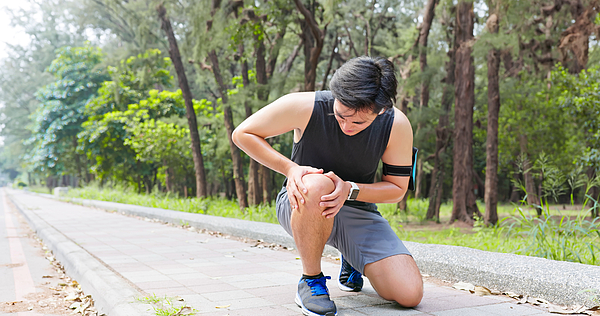

knee health tips